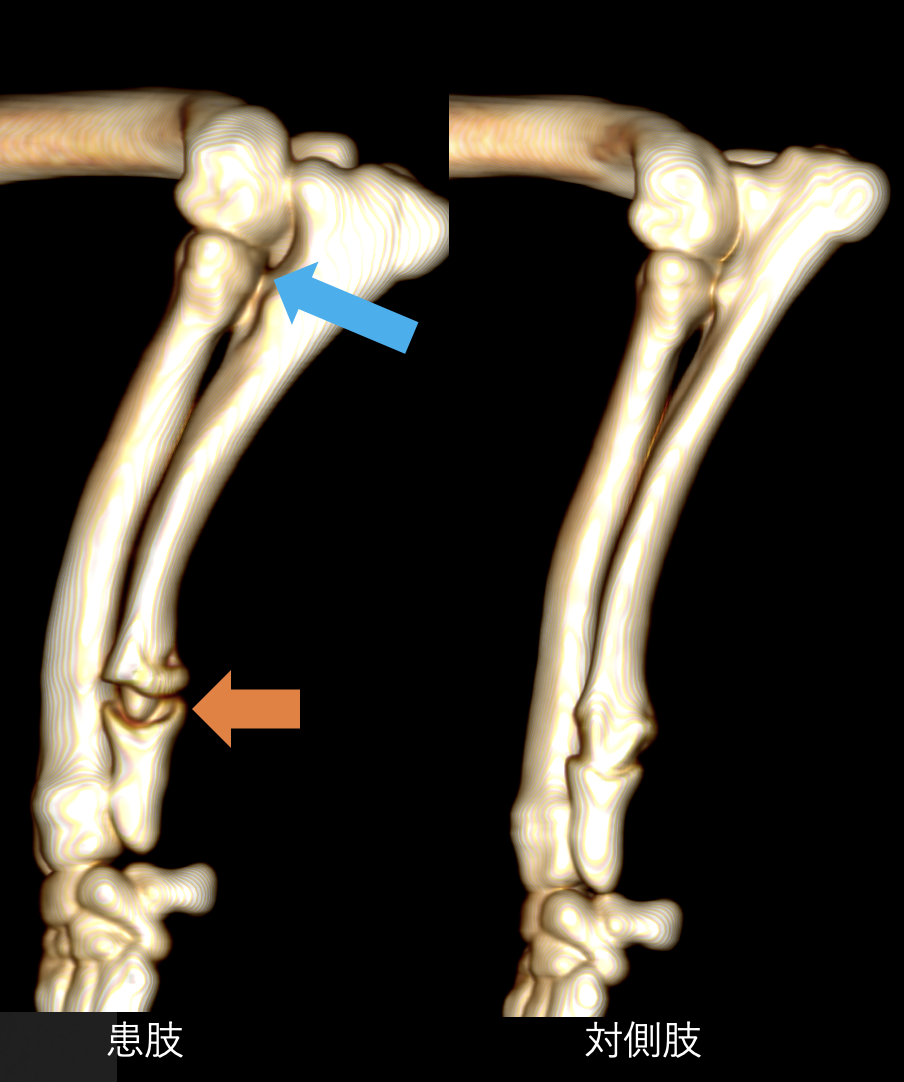

X線画像です。左が患肢で、右が正常肢です。2本ある骨のうち、左が橈骨、右が尺骨といいます。患肢の尺骨遠位成長板が少し黒っぽくなっています。よく見ると肘の尺骨がずれているのが分かります。

CT画像検査です。オレンジ色の矢印が、尺骨の成長板ですが、反対と比べると形態が異常なのが分かります。また、尺骨の成長板に障害を受けたために、尺骨が橈骨に比べ短くなっており、肘の関節がずれてしまっています(青矢印)。